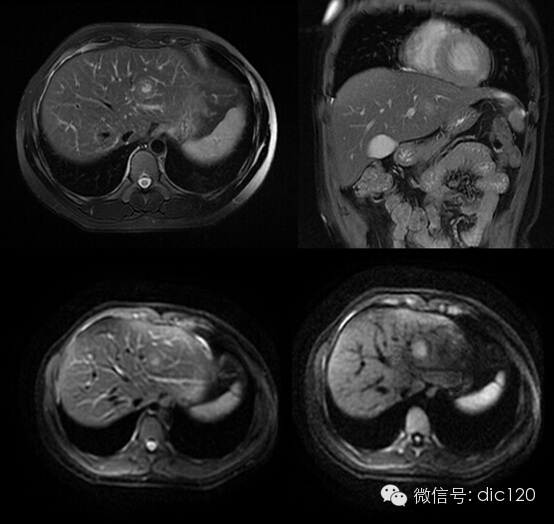

影像表現(xiàn):CT平掃與正常肝組織呈等密度,密度均勻,動(dòng)脈期病灶快速明顯均勻強(qiáng)化,中心見(jiàn)小片狀低密度影(瘢痕),門(mén)脈期及延遲期對(duì)比劑快速退出呈等密度,中央低密度影延遲強(qiáng)化。MRI腫塊T2WI為稍高信號(hào),中央高信號(hào)。動(dòng)態(tài)增強(qiáng)掃描動(dòng)脈期均顯著增強(qiáng),門(mén)脈期輕度增強(qiáng),延遲期瘢痕強(qiáng)化。

FNH具有離心性血液供應(yīng)及二條血液引流途徑。FNH的典型CT表現(xiàn)包括增強(qiáng)早期腫瘤呈彌漫均勻強(qiáng)化,在門(mén)靜脈期或門(mén)靜脈后期成等密度,病灶內(nèi)可見(jiàn)中心低密度瘢痕及輻射狀分隔,腫瘤周圍有薄而不完整的包膜樣血管。瘢痕是FNH 另一個(gè)重要影像學(xué)表現(xiàn),尤其是延遲掃描瘢痕強(qiáng)化為其特征。